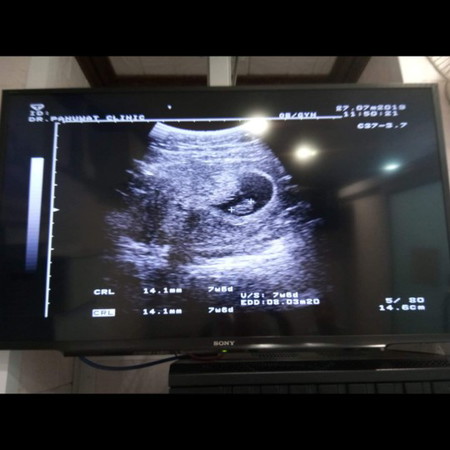

คำนวณอายุครรภ์

การคำนวณอายุครรภ์จะดูจากผลซาวน์หรือจากที่หมอนับเป็นหลักคะ

เครื่องอัลตราซาวด์คาดคะเนจากขนาดของตัวอ่อน ในขณะที่คุณหมอนับจากวันแรกของประจำเดือนครั้งล่าสุดค่ะ

ผลซาวน์มีความแม่นยำกว่าค่ะ